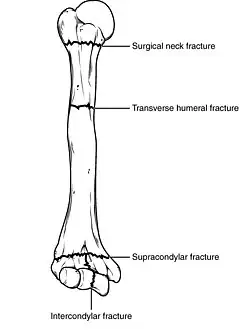

Fractures of the humerus are classified based on the location of the fracture and then by the type of fracture. There are three locations that humerus fractures occur: at the proximal location, which is the top of the humerus near the shoulder, in the middle, which is at the shaft of the humerus, and the distal location, which is the bottom of the humerus near the elbow.[9] Proximal fractures are classified into one of four types of fractures based on the displacement of the greater tubercle, the lesser tubercle, the surgical neck, and the anatomical neck, which are the four parts of the proximal humerus, with fracture displacement being defined as at least one centimeter of separation or an angulation greater than 45 degrees. One-part fractures involve no displacement of any parts of the humerus, two-part fractures have one part displaced relative to the other three; three-part fractures have two displaced fragments, and four-part fractures have all fragments displaced from each other.[13][14][3] Fractures of the humerus shaft are subdivided into transverse fractures, spiral fractures, "butterfly" fractures, which are a combination of transverse and spiral fractures, and pathological fractures, which are fractures caused by medical conditions.[12] Distal fractures are split between supracondylar fractures, which are transverse fractures above the two condyles at the bottom of the humerus, and intercondylar fractures, which involve a T- or Y-shaped fracture that splits the condyles.[7]